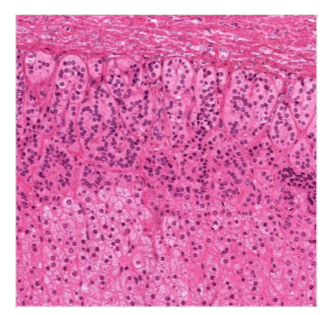

stomach